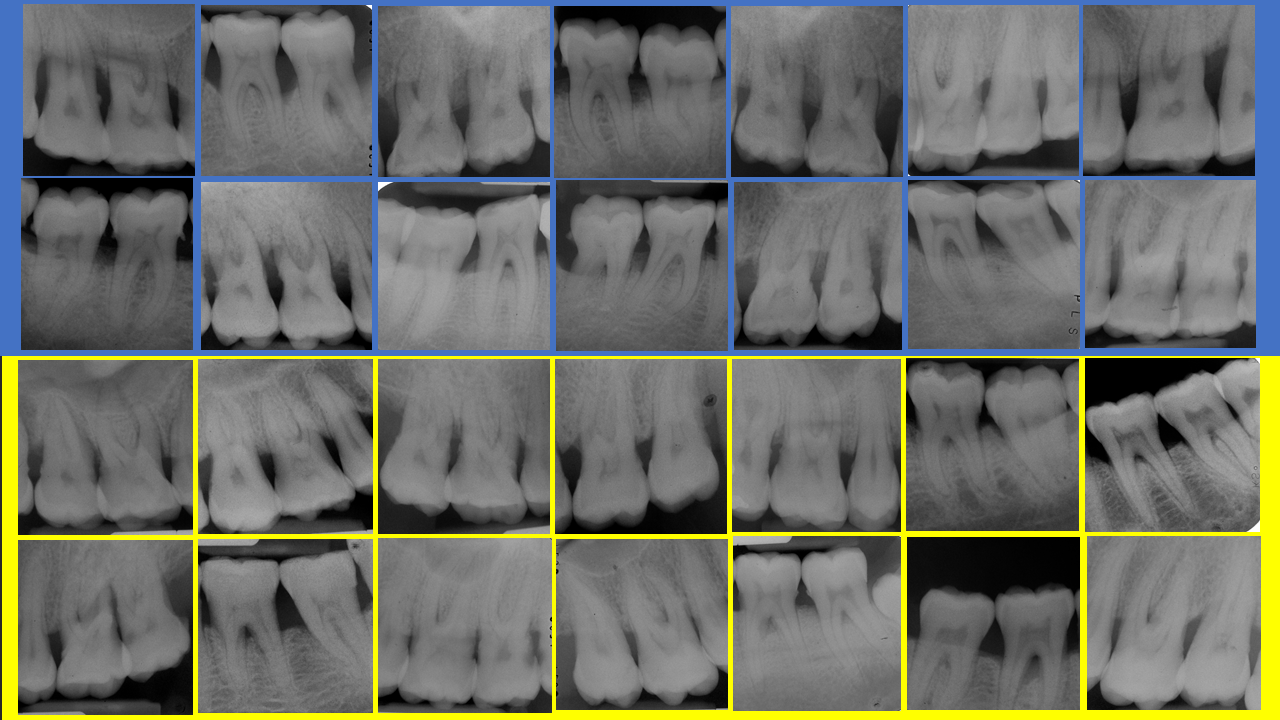

Más de 65.000 datos analizados en 500 pacientes durante 25 años.

La base de datos de este modelo predictivo figura entre las muestras más amplias monitorizando la pérdida dentaria en pacientes que cumplen con las revisiones de mantenimiento (Martinez-Canut, P. (2015) Predictors for tooth loss due to periodontal disease in patients following long-term periodontal maintenance. Journal of Clinical Periodontology 42, 1115-1125).

Cerca de 20 factores predictivos de pérdida dentaria se analizaron con diferentes pruebas estadísticas en busca de consistencia de los resultados. Once de estos factores, más claramente asociados con la pérdida dentaria, se seleccionaron finalmente para construir el modelo predictivo.